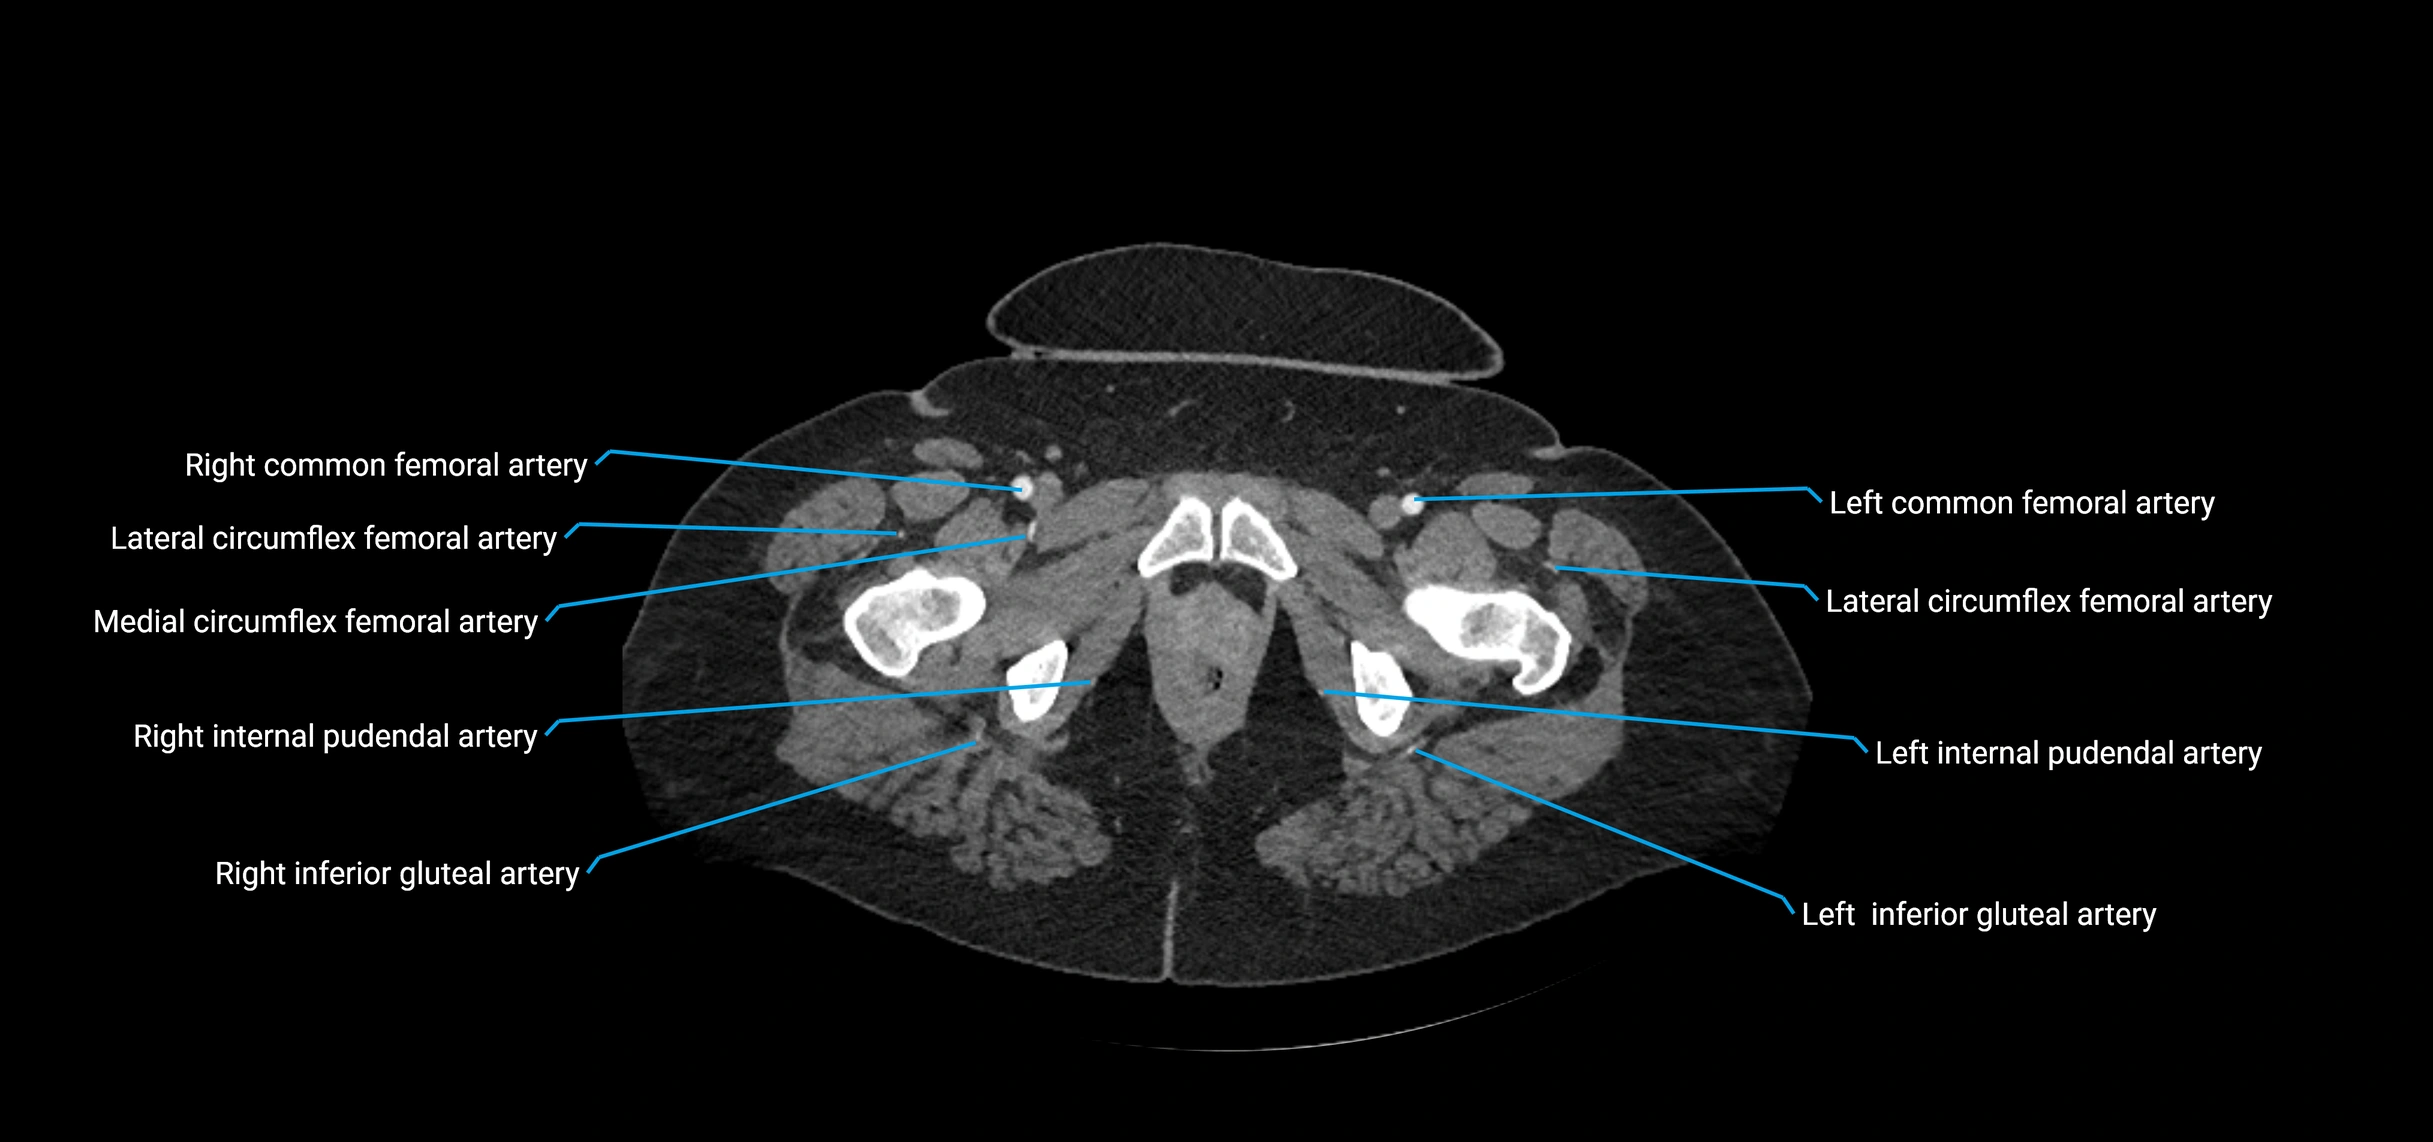

CT Appearance

Non-contrast CT:

• Appears as a tubular soft tissue structure anterior to vertebral bodies

• Calcified atherosclerotic plaques appear as hyperdense foci along the wall

• Useful for screening abdominal aortic aneurysm (AAA) size and mural calcification

Contrast-enhanced CT (CTA):

• Gold standard for abdominal aortic imaging

• Provides excellent detail of lumen, wall, aneurysm, thrombus, and branch vessels

• Multiplanar and 3D reconstructions help in aneurysm measurement, stent graft planning, and dissection evaluation

• Detects acute rupture, traumatic injury, or occlusion with high sensitivity

CT images

image